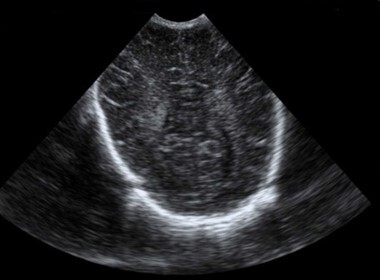

Neonatology Ventricle Asymmetry 4 Image